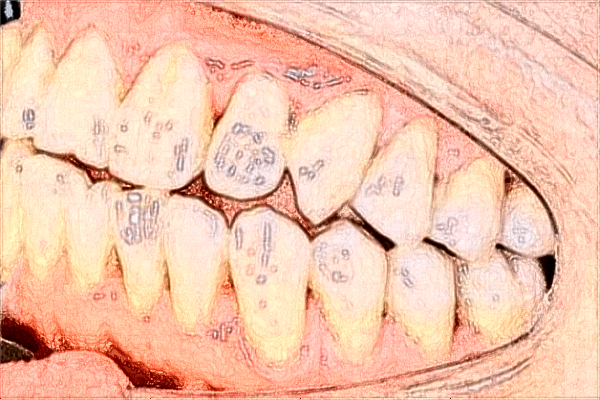

南寧市第一人民醫(yī)院口腔科案例

不知道是什么原因造成的,從今年開始就發(fā)現(xiàn)自己的牙齒有了發(fā)黃的跡象,其實也沒有特殊的愛好,比如說抽煙喝酒,可是牙齒還是有一些發(fā)黃的跡象,因此有了美容整形的想法,去了南寧市第一人民醫(yī)院口腔科和醫(yī)生說了我的訴求之后,醫(yī)生說可以通過洗牙的方法來,如今洗牙的技術(shù)是特別成熟的,像我這樣的現(xiàn)象有可能是因為喝茶水導(dǎo)致的,因為長時間喝茶水也會有黑色素沉積,使牙齒有了發(fā)黃的跡象,因此醫(yī)生就給我做了洗牙,在洗牙的時候稍微有一些陣痛的感覺,但是洗完牙齒之后真的讓我特別驚訝,牙齒相當(dāng)白,看上去很漂亮。